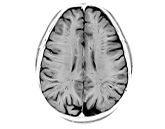

Marro Laboratory Research Team News Gallery Research The Marro Lab investigates the molecular mechanisms underlying human brain development and disease using stem cell–based models and genetic engineering. We focus on induced pluripotent stem cells (iPSCs) and...